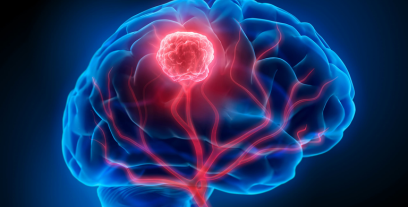

Brain tumors can be life-altering diagnoses, and timely treatment can make all the difference in a patient’s prognosis. When it comes to specialized care in neurosurgery, particularly brain tumor treatment, Dr. Atmaranjan Dash stands out as a leading expert in Bhubaneswar. With his extensive qualifications and a focus on minimally invasive techniques, Dr. Dash is committed to providing patients with the highest level of care.

Brain tumor treatment includes a comprehensive approach tailored to each patient. This may involve:

– Diagnosis: Advanced imaging techniques such as MRI and CT scans to accurately locate and identify the tumor type.

– Surgical Intervention: Both traditional and minimally invasive surgical techniques to excise the tumor.

– Adjuvant Therapy: Coordination with oncologists for chemotherapy and radiotherapy, when necessary.